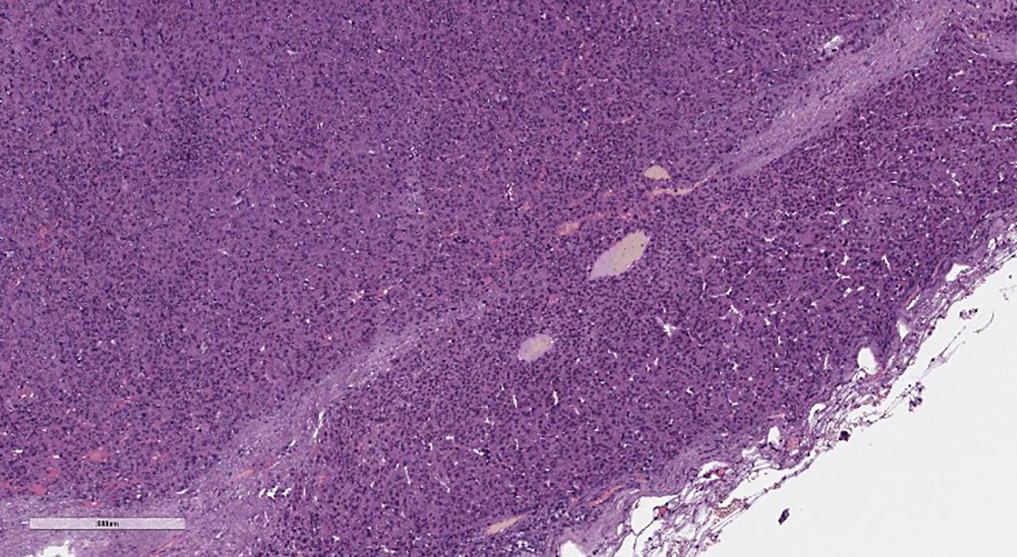

Учитывая двустороннее поражение надпочечников, было принято решение первым этапом провести удаление большего по размеру образования. В декабре 2017 г. выполнена лапароскопическая адреналэктомия справа. В послеоперационном периоде назначена заместительная терапия гидрокортизоном в дозе 25 мг/сут. Морфологическое исследование послеоперационного материала: в исследуемом материале определяются фрагменты опухоли, преимущественно солидного строения, из крупных клеток с обильной эозинофильной зернистой цитоплазмой, с крупными полиморфными ядрами, некоторые из них содержат псевдовключения; в опухоли отмечаются признаки неполной капсулярной инвазии, мелкие фокусы некроза, кровоизлияния и очаги фиброза. Результаты иммуногистохимического исследования: выраженная позитивная реакция опухолевых клеток с антимитохондриальными антителами (рис. 4), позитивная реакция опухолевых клеток с меланом А (рис. 5), ингибином А (рис. 6), отрицательная реакция с хромогранином, индекс пролиферации Ki67 составил 4%. По системе Lin–Weiss–Bisceglia (LWB) для онкоцитарных адренокортикальных опухолей выявлены 2 малых критерия — инвазия в капсулу и некрозы (рис. 7), что свидетельствует в пользу адренокортикальной онкоцитарной опухоли с неопределенным злокачественным потенциалом.

Рисунок 7. Микроскопическая картина удаленной опухоли правого надпочечника. Окраска гематоксилином и эозином. Увеличение ×100.

Окончательный диагноз основывается на гистологическом и иммуногистохимическом анализе послеоперационного материала, однако существуют трудности морфологической диагностики, так как классификация Weiss не применима в случае адренокортикальных онкоцитом [27]. В связи с этим в 2004 г. была разработана модифицированная система Lin–Weiss–Bisceglia (LWB) для оценки степени злокачественности адренокортикальных онкоцитом, которая включила: (1) большие критерии: частота митозов >5 на 50 полей, любые нетипичные митозы или венозная инвазия; (2) малые критерии [большой размер (>10 см и/или вес >200 г), некроз, инвазия капсулы или синусов]; (3) морфологические критерии онкоцитарных клеток (преимущественно клетки с эозинофильно-гранулярной цитоплазмой, высоким ядерно-цитоплазматическим соотношением и диффузным архитектурным рисунком) [28]. Наличие одного из больших критериев указывает на злокачественность (онкоцитарная адренокортикальная карцинома), в то время как наличие по меньшей мере одного малого критерия говорит о неопределенном (пограничном) злокачественном потенциале. Отсутствие признаков свидетельствует о доброкачественном образовании (адренокортикальная онкоцитома) [18]. Иммуногистохимическое исследование помогает определить природу опухоли и злокачественный потенциал.

9. Рисунок 7. Микроскопическая картина удаленной опухоли правого надпочечника. Окраска гематоксилином и эозином. Увеличение ×100. | |